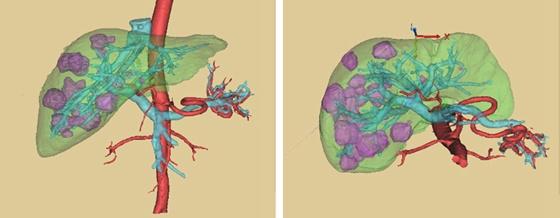

原发性肝癌也是肝脏结节的一种,原发性肝癌指的是肿瘤由肝脏里的细胞发生恶变产生的。包括原发性肝细胞癌,胆管细胞癌,以及混合细胞癌。我国是肝炎大国,大部分肝癌都是继发于肝炎,肝硬化。近年来,酗酒的人群增多,继发于酒精性肝硬化的患者也不少。长期饮酒,有慢性乙肝、丙肝、脂肪肝的患者,一定要定期查肝脏彩超,抽血化验甲胎蛋白AFP。早期的肝癌以手术和射频治疗为主,晚期肝癌以介入治疗,靶向治疗为主。

肝转移癌是指其他地方的肿瘤,转移到肝脏,例如乳腺癌,结直肠癌,肺癌都可以转移到肝脏。因为肝脏的血流非常丰富,肿瘤细胞可以通过血流转移到肝脏。如果出现了肝脏转移,一般就属于肿瘤晚期了,以化疗和靶向治疗为主。